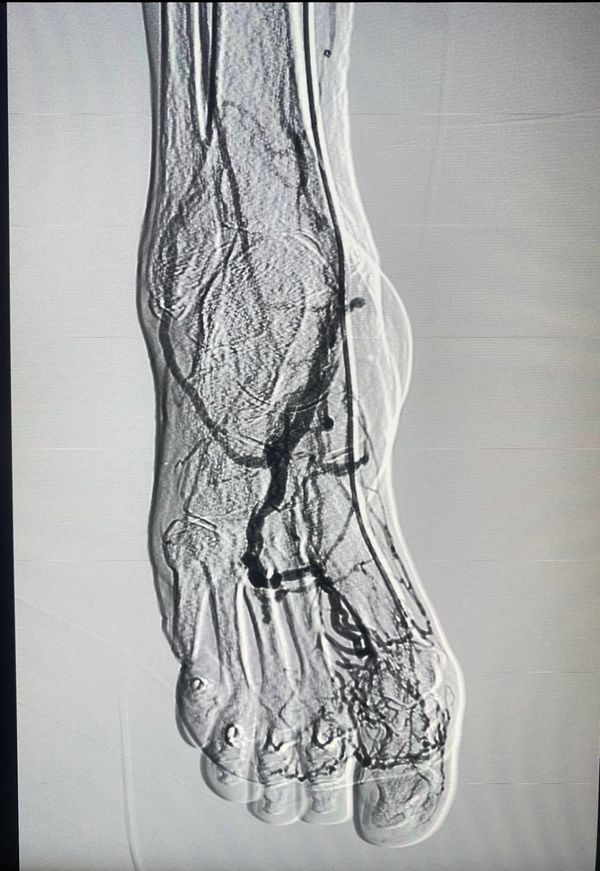

Angiólogos certificados, especialistas en el tratamiento de mínima invasión de la enfermedad venosa crónica (Várices ) , fleboestética , salvamento del pie diabético, manejo avanzado de heridas crónicas, Aneurismas , Fístulas Arteriovenosas y todo lo relacionado a los problemas de la circulación.